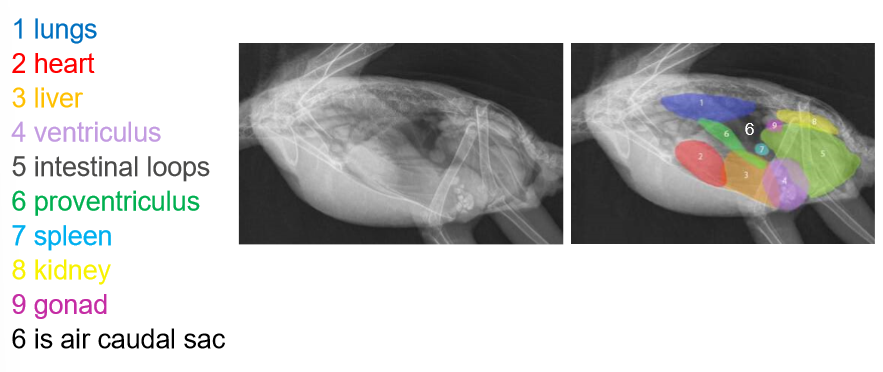

• label the image

A) lungs

B) heart

C) liver

D) ventriculus

E) intestines

F) proventriculus

G) spleen

H) kidney